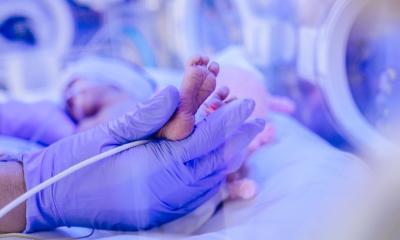

AI helps spot signs of dysplasia in infant hips

Developmental dysplasia of the hip occurs in 2-4% of infants, but screening via ultrasound is notoriously hard to master. An AI-assisted application could prevent many unnecessary hospital referrals.